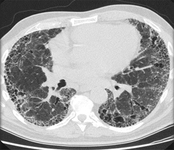

Exploración por TC de tórax de un paciente con toxicidad pulmonar por amiodarona, que muestra opacidades asimétricas con una distribución periférica

De la colección personal del Dr. A. Pataka y el Profesor P. Argyropoulou, Aristotle University, Thessaloniki, Grecia